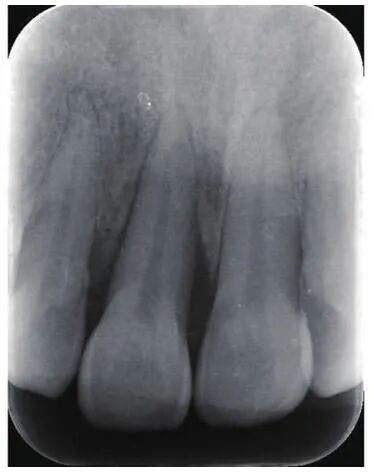

作为最基础的牙片,根尖片一般的普通门诊医院都可以拍,费用也相对低廉。

其优点在于

1

:

比例,真实再现口腔内牙齿牙龈牙骨等的相对位置等情况,不会把牙齿放大缩小,缺点是一次只能拍到

1-3

颗牙齿。

它可以帮助牙医确定个别牙齿龋坏

(

龋齿,俗称蛀牙

)

程度、炎症扩散范围、牙齿周围骨头状况、隔壁牙齿情况等等。